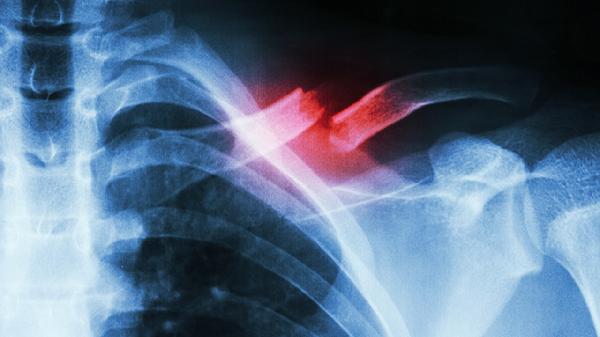

肋软骨炎可遵医嘱使用布洛芬缓释胶囊、双氯芬酸钠缓释片、塞来昔布胶囊、盐酸氨基葡萄糖胶囊、洛索洛芬钠片等药物缓解症状。肋软骨炎通常由外伤、慢性劳损或病毒感染等因素引起,表现为局部疼痛、肿胀及压痛感,药物选择需结合病因及个体差异。

肋软骨炎患者除药物治疗外,应避免胸部剧烈运动或负重,可局部热敷促进血液循环。睡眠时选择仰卧或健侧卧位减轻患侧压力,均衡饮食补充蛋白质和维生素C有助于组织修复。若疼痛持续超过两周或伴随发热、呼吸困难等症状,需及时复查排除其他胸廓疾病。所有药物均需在医生指导下使用,不可自行增减剂量或更换药物。